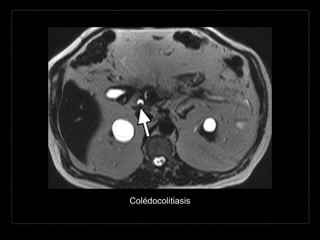

Hallazgos por RM

• CPRM (RARE - HASTE)

• bilis: muy hiperintensa

• cálculos: foco hipointenso

• defectos de llenado

hipointensos entre la bilis

hiperintensa.

• T1

• apariencia variable.

CPRM

Colédocolitiasis